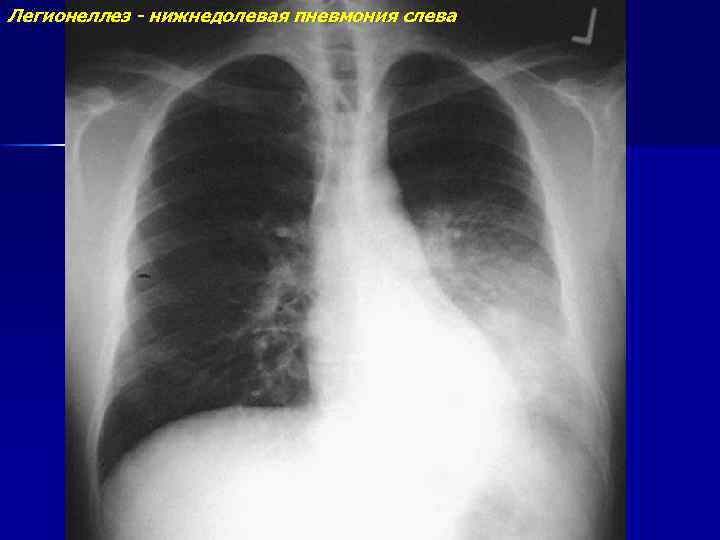

Болезнь легионеров (легионеллез)

Легионеллез - нижнедолевая пневмония слева

Легионеллез - нижнедолевая пневмония слева (продолжение)